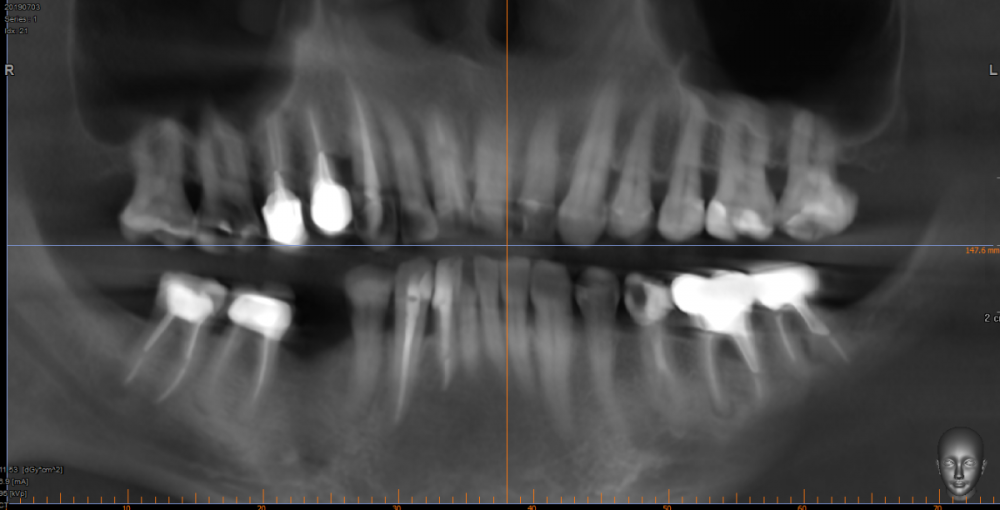

Jonik Опубликовано 24 апреля, 2022 Поделиться Опубликовано 24 апреля, 2022 Здравствуйте! У меня клиновидный дефект, убыль костной ткани и рецессии десны. Было несколько консультаций у ортодонтов, мнения разные: 1) Брекеты ставить нельзя, недостаточно костной ткани, брекеты усугубят ситуацию; 2) Брекеты можно поставить, но результат непредсказуем, можно потерять зубы (передние нижние); 3) Брекеты поставить можно и нужно или будет хуже. Прошу вашего совета как поступить, у меня два вопроса: 1) Нужны ли мне брекеты, помогут ли они в моем случае; 2) Можно ли установить мне брекеты, учитывая объем кости и тд. Есть КТ по ссылке https://drive.google.com/drive/folders/1zs22D5kDglz_UOtPfKQ2lUmh8P5N8cv7?usp=sharing Ссылка на комментарий

art700 Опубликовано 26 апреля, 2022 Поделиться Опубликовано 26 апреля, 2022 Можно. Но придётся закрывать рецессии, возможно и до брекетов и после. Ссылка на комментарий